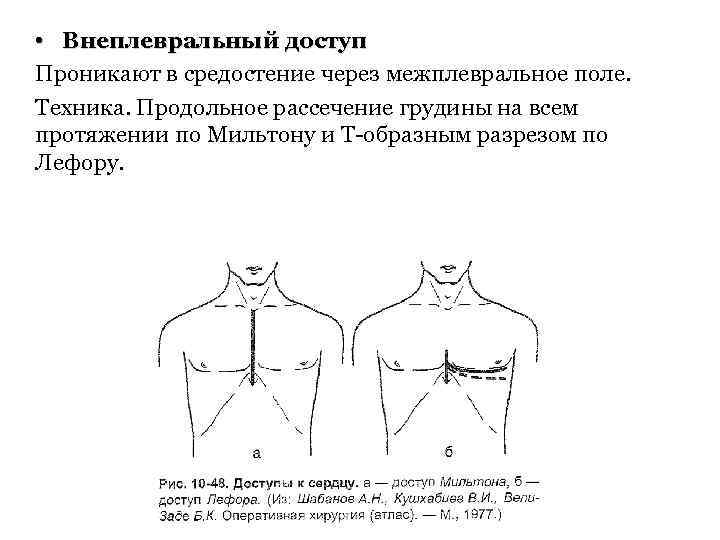

• Внеплевральный доступ Проникают в средостение через межплевральное поле. Техника. Продольное рассечение грудины на всем протяжении по Мильтону и Т-образным разрезом по Лефору.

• Внеплевральный доступ Проникают в средостение через межплевральное поле. Техника. Продольное рассечение грудины на всем протяжении по Мильтону и Т-образным разрезом по Лефору.